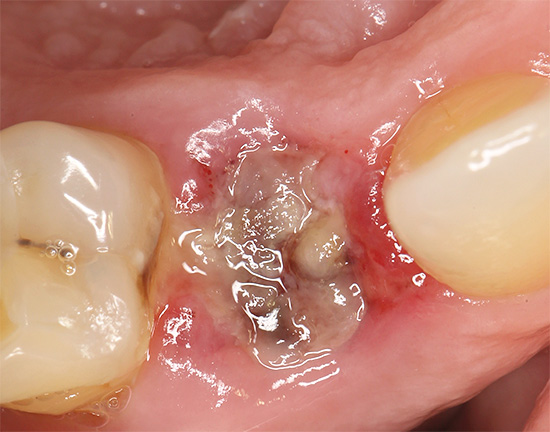

A foto abaixo mostra como o buraco fica logo após a remoção do dente do siso, anteriormente escondido sob a gengiva: